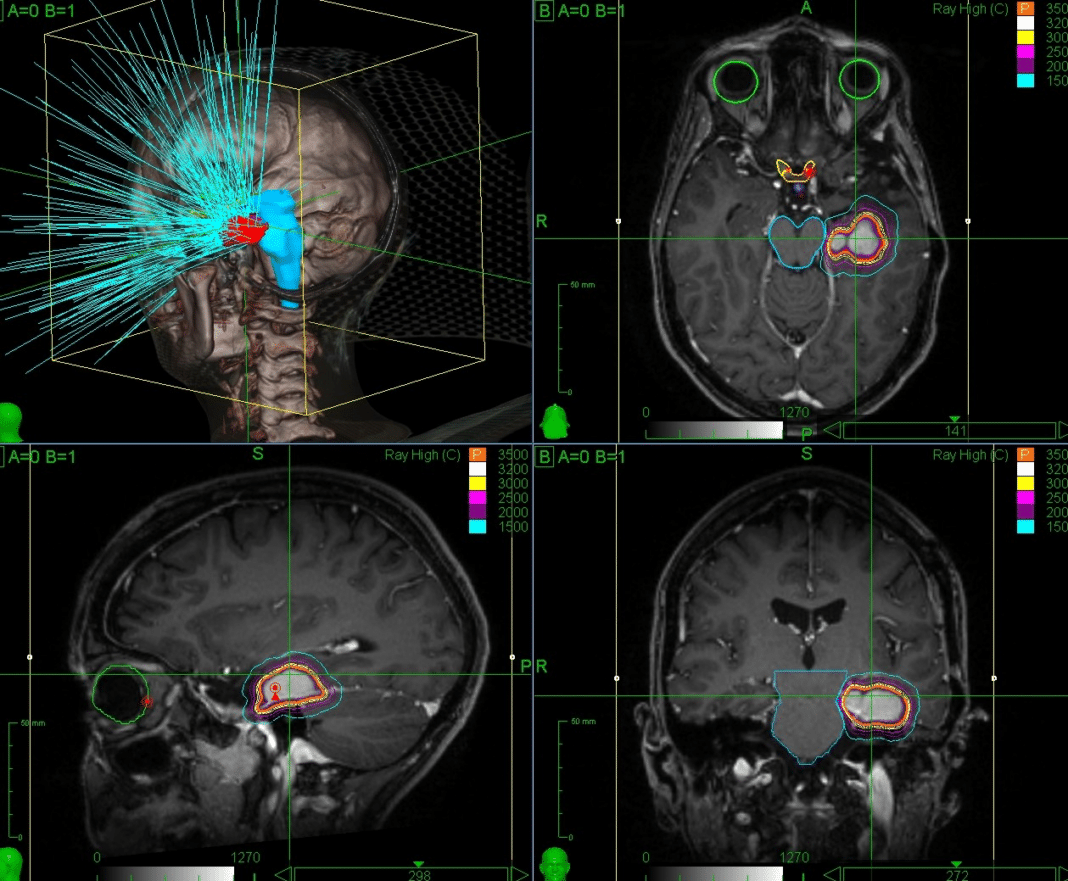

Ριζική θεραπεία για καρκινικούς όγκους, αγγειακές δυσπλασίες και νευροχειρουργικές διαταραχές, υπόσχεται η ακτινοχειρουργική, μια μη επεμβατική μέθοδος που χρησιμοποιεί ακτινοβολία υψηλής ακρίβειας (κάτω του 1mm). Συγκριτικά με την νευροχειρουργική και την ακτινοθεραπεία, η ακτινοχειρουργική, σύμφωνα με τους ειδικούς, αποτελεί σήμερα μια αξιόπιστη θεραπευτική επιλογή προσφέροντας το βέλτιστο θεραπευτικό αποτέλεσμα, με τις λιγότερες παρενέργειες.

Η θεματολογία του 1st CNS Radiosurgery Athens Meeting θα εστιαστεί στις θεραπείες παθήσεων του εγκεφάλου και του νωτιαίου μυελού και ειδικότερα για ακουστικό νευρίνωμα, μηνιγγιώμα, αδένωμα υπόφυσης, σπάνιους όγκους της βάσης του κρανίου (χόρδωμα-χονδροσάρκωμα), αρτηριοφλεβώδεις δυσπλασίες (AVM), αιμαγγείωμα, εγκεφαλικές μεταστάσεις, υποτροπές γλοιωμάτων, νευραλγία τριδύμου , σπαστικότητα και ψυχικές διαταραχές.

Ακτινοχειρουργική: Η μη επεμβατική μέθοδος ριζικής θεραπείας για καρκινικούς όγκους, αγγειακές δυσπλασίες και νευροχειρουργικές διαταραχές